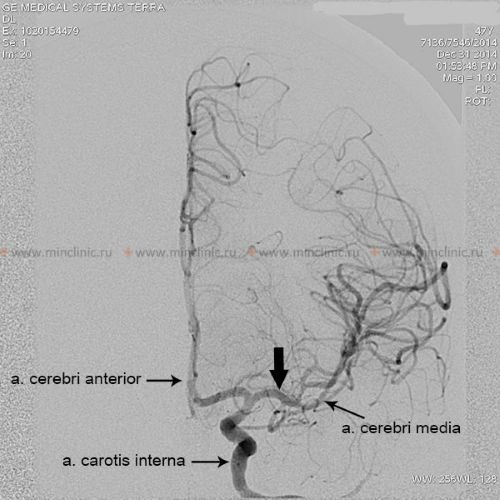

If cerebral artery embolism is suspected, identifying the location of the arterial occlusion and assessing the downstream brain tissue is critical for guiding acute treatment (like thrombectomy) [16, 19]. Non-invasive vascular imaging, such as CT angiography (CTA) or MR angiography (MRA), is typically performed urgently [16]. Conventional catheter-based cerebral angiography (Digital Subtraction Angiography - DSA) provides the highest resolution detail of the vessels but is invasive [14]. It may be performed if endovascular treatment (thrombectomy) is planned or if non-invasive imaging is inconclusive [16, 19]. It's important to note that after several hours or days, an embolus might migrate distally, fragment, or undergo spontaneous lysis (dissolution), meaning that angiography performed later might not show the original occlusion, making the definitive diagnosis of embolic stroke sometimes presumptive based on clinical presentation and infarct pattern [1]. Standard intravenous contrast administration during a routine CT or MRI scan generally lacks the resolution and timing necessary to directly visualize small cerebral emboli within vessels [14].